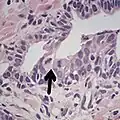

-

Intraductal carcinoma of the prostate with very patchy basal cells identified by immunohistochemistry. At least some of the glands lacking basal cell immunoreactivity represent intraductal rather than invasive carcinoma (a haematoxylin and eosin, b CK 5/6)[20]